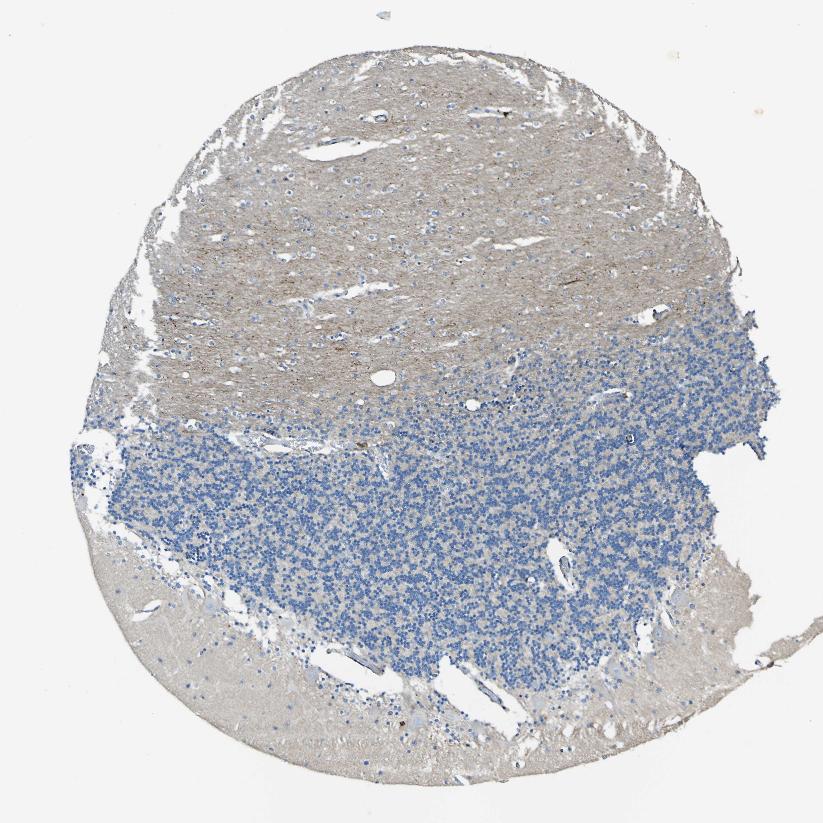

CEREBELLUM - Antibody stainingi

Antibody staining in the annotated cell types in the current human tissue is reported as not detected, low, medium, or high, based on conventional immunohistochemistry profiling in selected tissues. This score is based on the combination of the staining intensity and fraction of stained cells.

Each image is clickable and will lead to virtual microscopy that enables deeper exploration of all samples and also displays staining intensity scores, fraction scores and subcellular localization as well as patient and tissue information for each sample.

Antibody HPA013132

Purkinje cells Not detected

Cells in granular layer Low

Cells in molecular layer Low